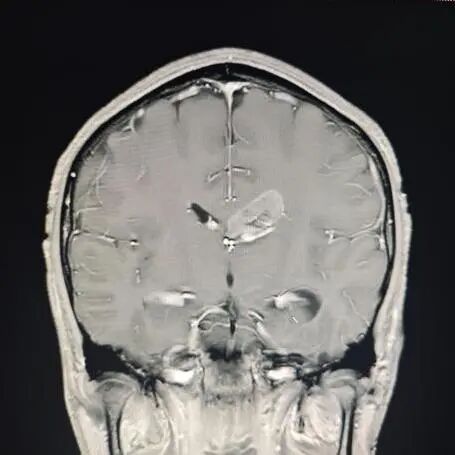

陆路副主任医师接诊后,为晓华做了详细检查。检查结果并不乐观:两年间,患者的肿瘤迅速生长至4厘米,挤压着左侧脑室后角空间。

"建议尽快手术!"诊室里,陆路副主任医师指着CT影像严肃地说道,"患者颅内的4厘米肿瘤已紧密压迫神经传导通路,若不及时处理,很可能导致脑脊液循环受阻,进而引发脑积水或肢体功能障碍。肿瘤每天都在生长,拖延只会让手术难度成倍增加。"这番解释让患者和家属深刻意识到病情的紧迫性。